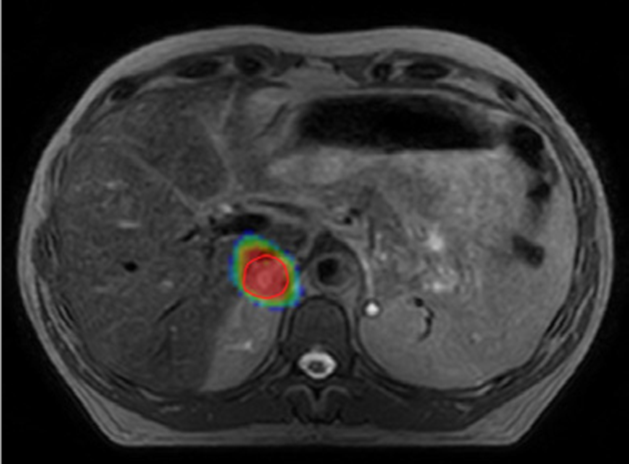

Key studies show that high-dose, image-guided SBRT delivers the stronger doses kidney tumors require, providing durable control with low side effects.

Kidneys can move by as much as 4 cm during normal breathing, so daily imaging and motion control are essential for accurate treatment and healthy-tissue protection.13

If surgery isn’t possible for people with localized kidney cancer, stereotactic MR-guided adaptive radiotherapy offers a safe, noninvasive treatment option with minimal impact on kidney function.11

Safely deliver high doses to improve clinical outcomes

Conventional SBRT can deliver curative doses, but kidney motion and daily anatomical changes make accuracy difficult. Adaptive radiotherapy and image-guidance address this by allowing you visualise and if needed, to adjust to those changes in real time. Adaptive workflows provide the precision needed to deliver the high, ablative doses required for radio-resistant kidney tumors, enabling you to improve outcomes safely and effectively.